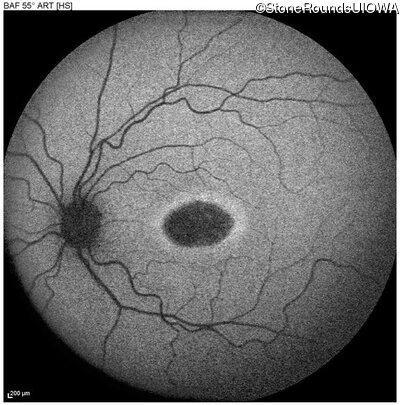

This 22 year old man had macular abnormalities noted incidentally at a routine eye exam at age 19. Since then, he has experienced a gradual loss of acuity particularly in the left eye.

| AR Stargardt Disease | ABCA4 | Tyr245Stop TAT>TAG | Unknown | AR |